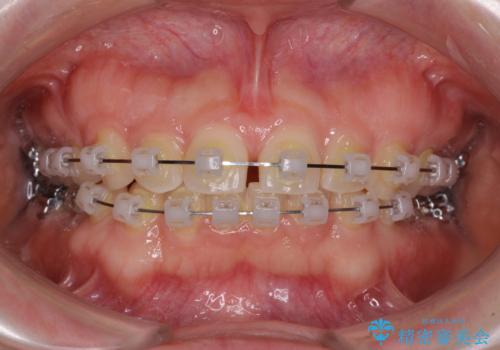

- クリアブラケット

ギリギリとなりましたが、結婚式直前にワイヤー装置を外すことができました。

ワイヤー装置除去後に細かい部分を短期間のマウスピース矯正にて仕上げました。